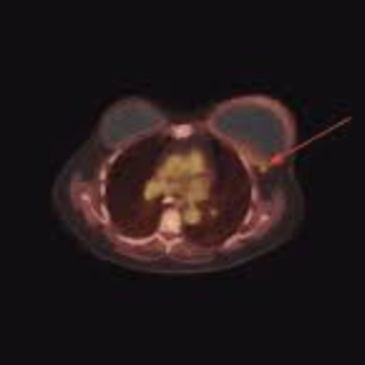

Principle: ^18F-FDG accumulates in metabolically active tumor tissue; fused PET–CT provides metabolic and anatomical correlation.

Indications:

Advantages:

Limitations:

Performance:

Clinical Value: